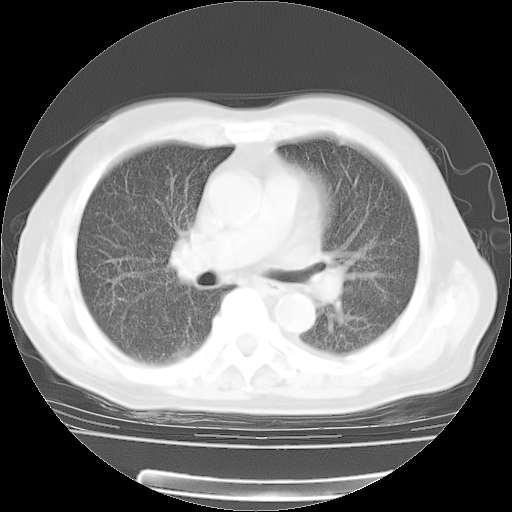

今天部分检查

轻微咳嗽,无痰,(体温正常时)R20次/分,P75次/分,双肺底、腋下可闻及少量捻发音。下肢轻度浮肿。

血常规:白细胞9.11×109/L,N0.92,L5.64,血小板39.2×109/L,HB148g/L,ESR2mm/H。

尿常规:潜血+

血生化:总蛋白69.71g/L,白蛋白38.40g/L,球蛋白31.31g/L,CRP27.9mg/L,尿素氮11.98mmol/L,肌酐106μmol/L,乳酸脱氢酶1099 U/L,肌酸激酶108U/L,CK-MB 61U/L。

腹部B超:胆囊壁增厚,肝、胆、胰、脾、肾无异常,肠系膜淋巴结、腹膜后淋巴结无增大。

ECG:右心室增大

心脏超声检查:无右心室增大。

增加治疗:异烟肼、利福平、乙胺丁醇,静滴左氧氟沙星、参麦注射液。甲强龙从80mg暂减为40mg。

强的松3月1日改为10mg qd,4月1日改为10mg qod。3月份以前的减量过程和环磷酰胺疗程需等明天查看记录(我岳父自己做的记录在他家里)。